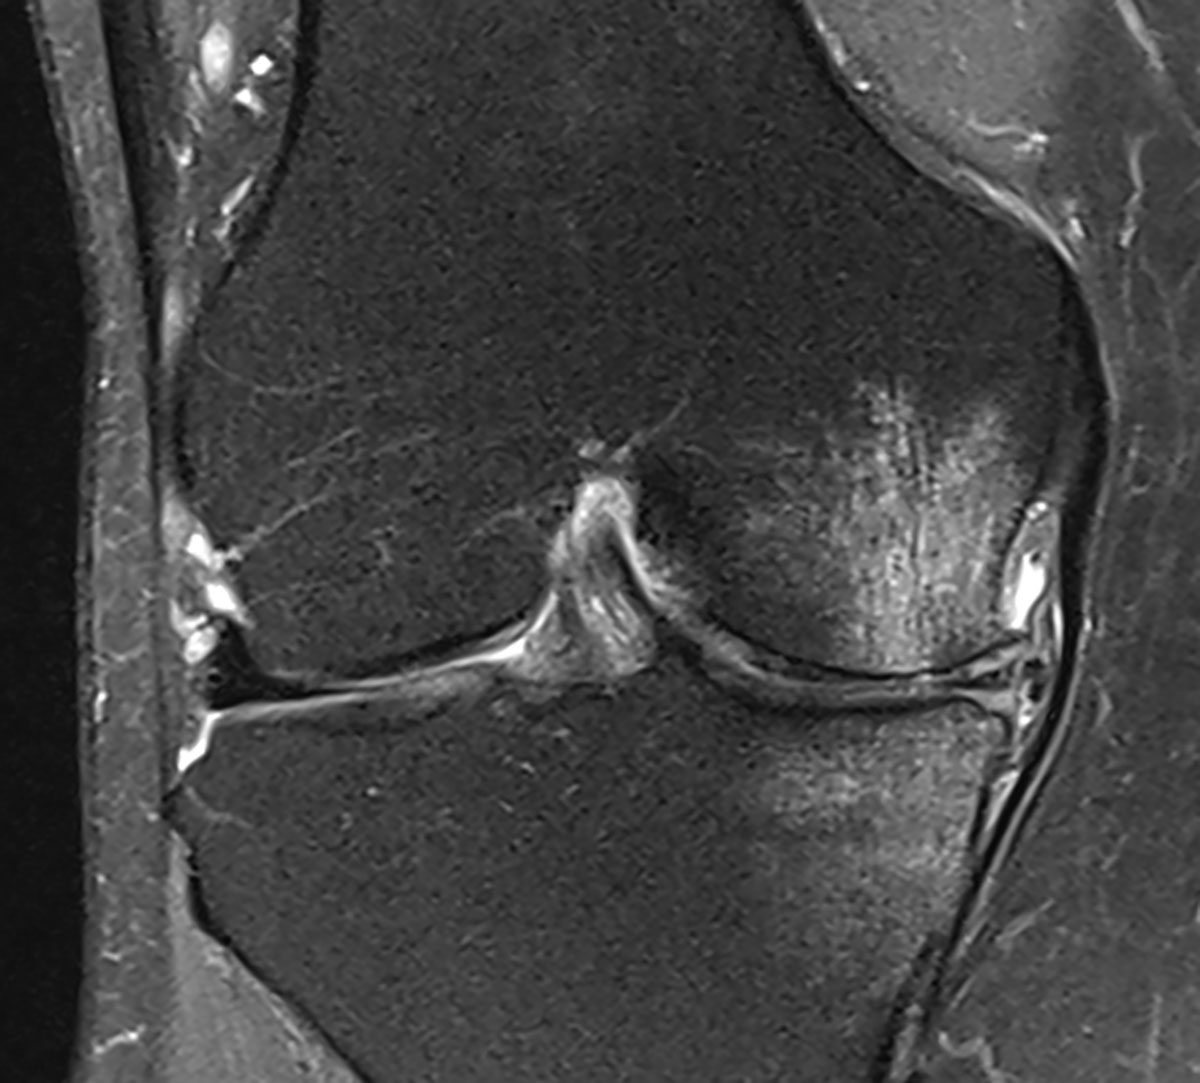

Es handelt sich bei der Patientin um eine uns bereits bekannte 64-jährige, aktive Patientin, die wir zuletzt im Frühjahr 2020 in unserer Praxis behandelt hatten. Die Patientin hat eine im Rahmen eines M. Ahlbäck vor einigen Jahren entwickelte, ausgeprägte Varusgonarthrose mit seinerzeit erheblichem Knochenödem (Abb. 2). Sie berichtete, dass sie seit unserer letzten Behandlung nahezu zwei Jahre weitestgehend beschwerdefrei gewesen sei und ihren Alltag einschließlich moderater sportlicher Aktivitäten gut bewältigen konnte. Nun musste sie sich im Rahmen der Haushaltsauflösung ihrer hochbetagten Mutter einer hohen körperlichen Belastung aussetzen, wodurch die Beschwerden wieder reaktiviert wurden. Ein aktuelles Kontroll-MRT hatte sie bereits durchführen lassen und bat um den schnellen Beginn einer neuen Behandlungsserie.

Das kürzlich durchgeführte MRT des rechten Kniegelenkes (06/2022) zeigt eine deutlich aktivierte Varusgonarthrose, aktuell wieder mit einer Zunahme des Knochenödems im Vergleich zu deren Voraufnahmen, einen Reizerguss sowie eine kleine Bakerzyste.